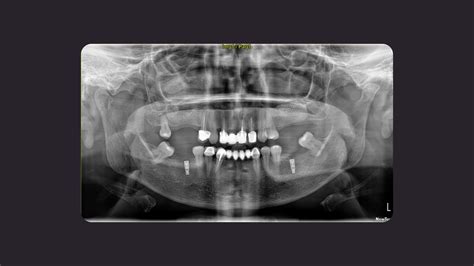

A la hora de realizar el diagnóstico, se debe realizar una exploración de las manifestaciones clínicas y radiológicas que presenta el paciente. El diagnóstico de sinusitis maxilar se basa en una evaluación clínica cuidadosa, en la que el médico recopila la historia médica del paciente y realiza una exploración física.

- A nivel radiológico, observamos un engrosamiento de la capa mucosa que tapiza los senos maxilares, posibles anomalías anatómicas, pólipos nasales etc.